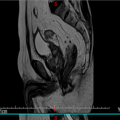

| 影像学检查:(点击查看大图) | 平扫:前列腺区见多发结节融合成团状异常信号,形态不规则、局部呈菜花状改变,边界欠清,范围约61mm×34mm×64mm,病变在T1WI上呈等信号,在T2WI上信号不均匀,呈等信号内见不规则团片状稍高信号,周围脂肪间隙模糊,病变与双侧精囊腺、膀胱后壁、直肠后壁、左侧闭孔内肌分界不清,直肠下段前部脂肪间隙消失,左侧精囊角消失;膀胱充盈欠佳,膀胱壁不规则稍增厚,最厚径约7mm。盆腔、双侧腹股沟、髂血管旁区见多发肿大淋巴结,较大大小约22mm×14mm。 增强:前列腺区见病变呈不均匀轻度环形强化,病变侵犯邻近直肠,相应肠管管壁增厚呈类似强化;盆腔、双侧腹股区、髂血管旁区肿大淋巴结呈轻度不均匀强化。增厚膀胱壁呈明显强化;余未见异常强化表现。 与2023-09-23 前列腺MRI对比:前列腺癌术后改变,前列腺区见多发结节融合成团状异常信号,新见左侧闭孔内肌、直肠后壁受累,左侧精囊角消失,髂血管旁区见多发肿大淋巴结,盆腔、双侧腹股沟淋巴结较前稍增多,其余所见大致相仿。 影像诊断意见: 前列腺癌(UICC分期:T4N1Mx IV期),双侧精囊腺、膀胱后壁、直肠后壁、左侧闭孔内肌受累,盆腔、双侧腹股沟、髂血管旁区见多发肿大淋巴结,复查病变较前进展。 |